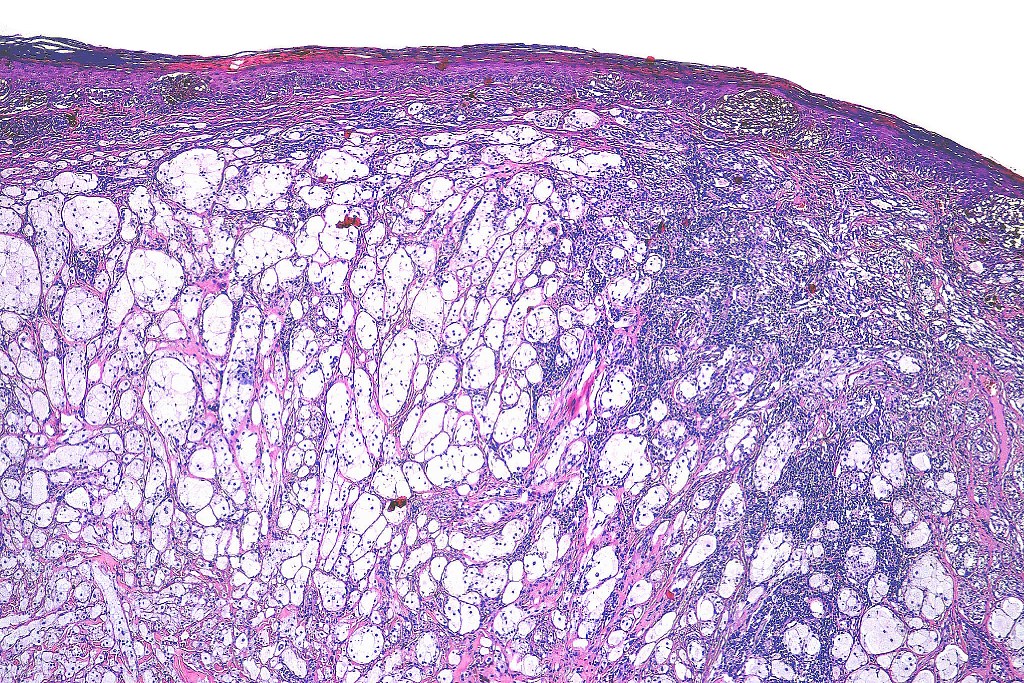

Clinical features

•Back> lower & upper extremities> head & neck> choroid

•Often ulcerated nodules

•Poor prognosis is likely related to large tumor size at presentation